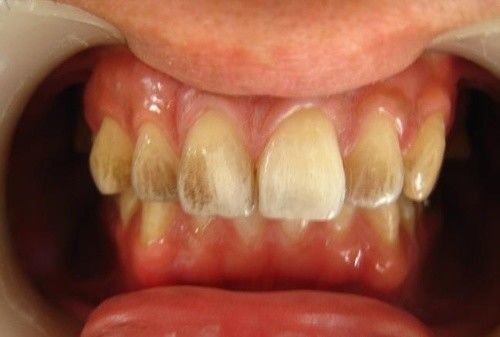

定期洗牙是目前最有效的治疗牙周疾病的方式。下面是洗牙前后的对比图:

洗牙(洁治)后,洁白如一